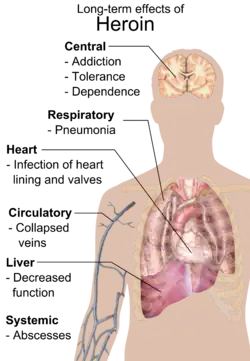

Long-term effects

Repeated heroin use changes the physical structure and physiology of the brain, creating long-term imbalances in neuronal and hormonal systems that are not easily reversed. Studies have shown some deterioration of the brain's white matter due to heroin use,[63] which may affect decision-making abilities, the ability to regulate behavior, and responses to stressful situations. Heroin also produces profound degrees of tolerance and physical dependence. Tolerance occurs when more and more of the drug is required to achieve the same effects. With physical dependence, the body adapts to the presence of the drug, and withdrawal symptoms occur if use is reduced abruptly.[61]

Injection

Intravenous use of heroin (and any other substance) with needles and syringes or other related equipment may lead to:

- Contracting blood-borne pathogens such as HIV and hepatitis via the sharing of needles

- Contracting bacterial or fungal endocarditis and possibly venous sclerosis

- Abscesses

- Poisoning from contaminants added to "cut" or dilute heroin

- Decreased kidney function (nephropathy), although it is not currently known if this is because of adulterants or infectious diseases[64]